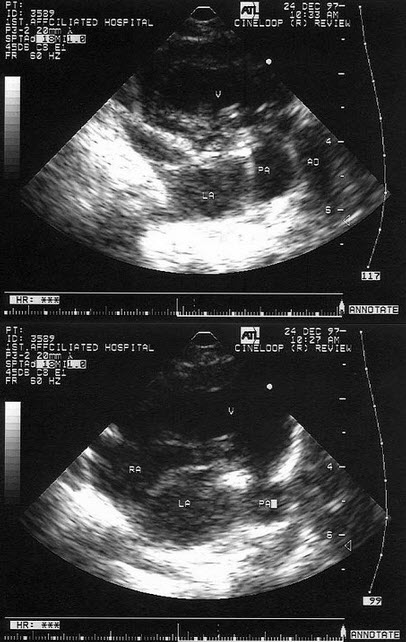

如图,二维超声心动图中,此为____________切面。

85、填空题 胎儿畸形包括__________、__________、___________、_____________、_____________、__________________、__________________、______________或___________等。